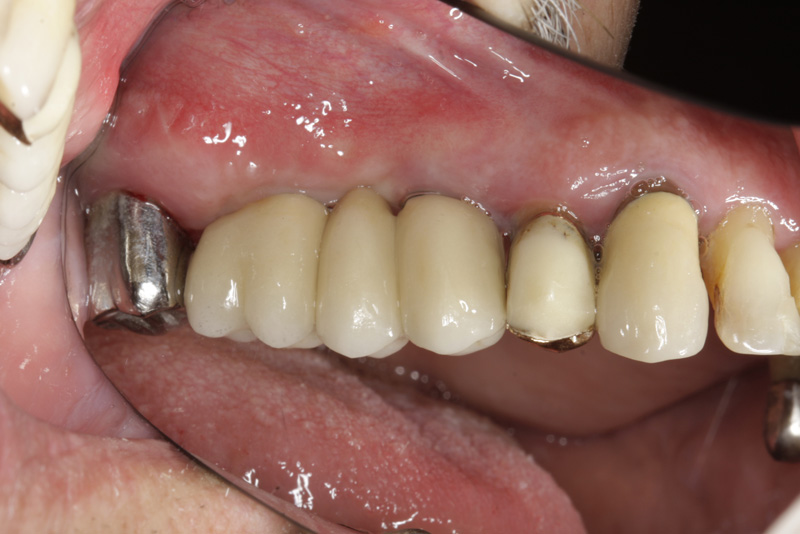

Protetické řešení může být pomocí můstku, který je kotvený na implantátech nebo pomocí jednotlivých korunek na implantátech.

V zásadě je možné do těchto můstků zařadit i přirozené zuby, zejména pokud je potřeba tyto zuby ošetřit proteticky

- korunkami. Korunky nebo můstky mohou být na implantáty nacementovány nebo přišroubovány.

Zdravé zuby zůstanou zachovány a přitom náhrady jsou pevné, jako na vlastních zubech